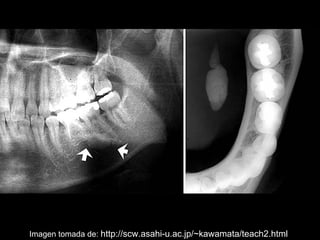

La sialolitiasis es la formación de obstrucciones mineralizadas en las glándulas salivales, causadas por el depósito de calcio y fósforo. Puede presentarse en las glándulas salivales mayores y menores, causando inflamación e hinchazón e incluso dolor durante las comidas. Los sialolitos se ven en radiografías como densidades radiopacas de varias formas y tamaños dentro de los conductos glandulares. El diagnóstico diferencial incluye otras imágenes radiopacas en los tejidos blandos.